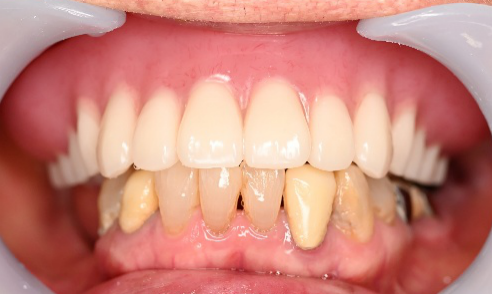

Before

After

【義歯を装着したところ】

【義歯を外したところ】